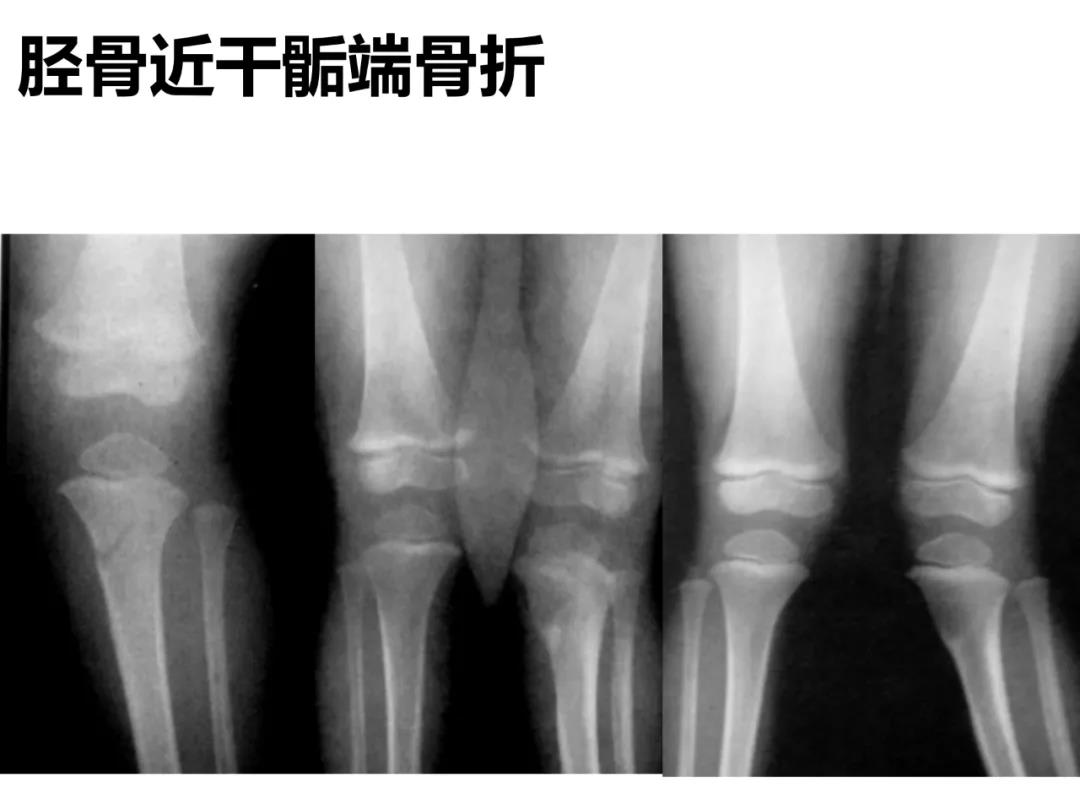

小儿骨科X线片汇总,临床读片宝典!